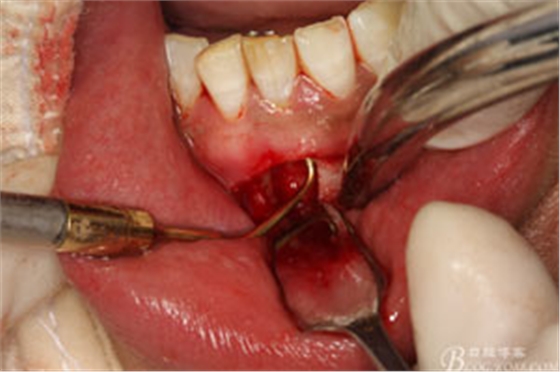

圖10.從唇側(cè)側(cè)穿除切除31根尖部分。